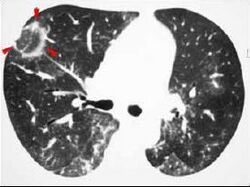

CT scan showing cryptogenic organizing pneumonia (biopsy-proven)

The reversed halo sign is seen in about 20% of individuals with COP.[18]

The chest x-ray is distinctive with features that appear similar to an extensive pneumonia, with both lungs showing widespread white patches. The white patches may seem to migrate from one area of the lung to another as the disease persists or progresses. Computed tomography (CT) may be used to confirm the diagnosis. Often the findings are typical enough to allow the doctor to make a diagnosis without ordering additional tests.[19] To confirm the diagnosis, a doctor may perform a lung biopsy using a bronchoscope. Many times, a larger specimen is needed and must be removed surgically.

Plain chest radiography shows normal lung volumes, with characteristic patchy unilateral or bilateral consolidation. Small nodular opacities occur in up to 50% of patients and large nodules in 15%. On high resolution computed tomography, airspace consolidation with air bronchograms is present in more than 90% of patients, often with a lower zone predominance. A subpleural or peribronchiolar distribution is noted in up to 50% of patients. Ground glass appearance or hazy opacities associated with the consolidation are detected in most patients.